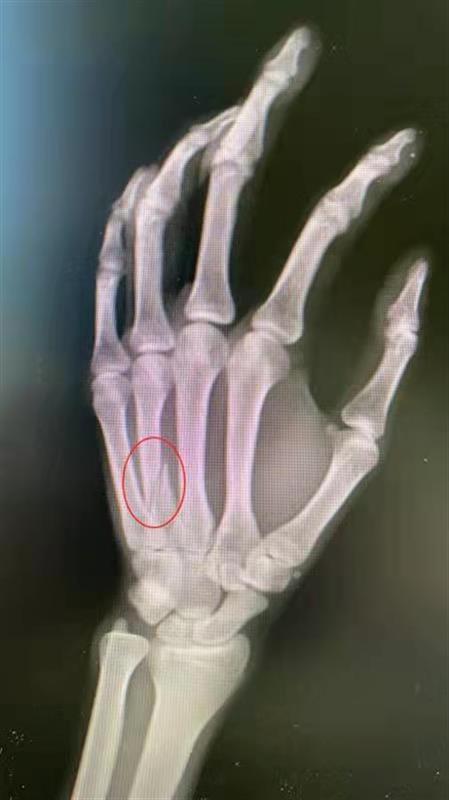

“右手第四掌骨,有明显的骨折,因为骨部位有旋转移位,需要手术固定。” 接诊的武汉市第四医院手外一科医生陈焱介绍, 像这种握拳后撞击硬物而导致骨折的,在医学上通常称为“拳击手骨折”,拳击手骨折是一种发生于掌骨的骨折。这种骨折很少发生在有拳套保护的职业拳击手身上,更多见于街头打斗中用“裸拳”打斗的人群。

“许多人认为拳头很硬,实际上手部掌骨与身体其他部位骨皮质相比,属于最薄的部位。所以当父亲的拳头打碰到儿子前臂肘关节时,骨皮质较薄的手掌骨会骨折。 ”该院手外一科主任邢丹谋介绍,“拳击手骨折”在临床中经常发生在年轻人中,一些年轻人容易冲动,往往生气后用拳击打墙壁,或是桌面,就会发生掌骨骨折。发生拳击手骨折后需要及时到医院治疗,否则会导致手指交指畸形,影响手部抓握功能。